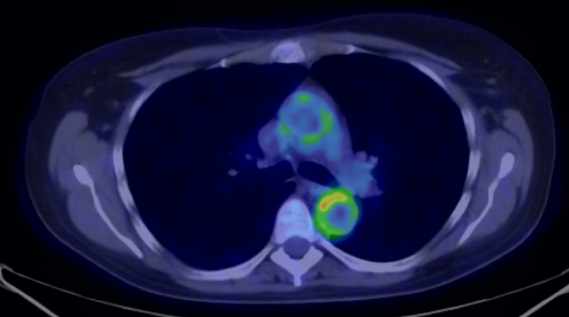

In the early phases of oncologic treatment (so called interim phase) PET examinations seem to be able to differentiate patients that respond well to the therapy, from the ones that are resistant to it. (Figure 12.)

12. Diffuse large B-cell lymphoma. Neoadjuvant staging (a-c) and after 3 cycles of immuno-chemotherapy, interim (d-f) FDG PET-CT. Maximum Intensity Projection (MIP) PET images (a,d), transversal fusion images (b,e) and CT images (c,f). During staging extended supra- and infradiaphragmatic nodal involvement was found. At the interim examination complete metabolic remission can be seen indicating a good therapeutic response. At the left parailiac region an extensive residual soft tissue mass can still be noted. (e-f).

In resistant cases this would provide valuable information, and ineffective, but expensive and toxic treatments could be suspended or modified. In addition, the intensity of FDG uptake and the level of early therapy response can also be useful in assessing prognosis. PET imaging due to its high sensitivity may be able to detect tumors of unknown origin (occult tumors), and with specific limitations it could be used for cancer screening.